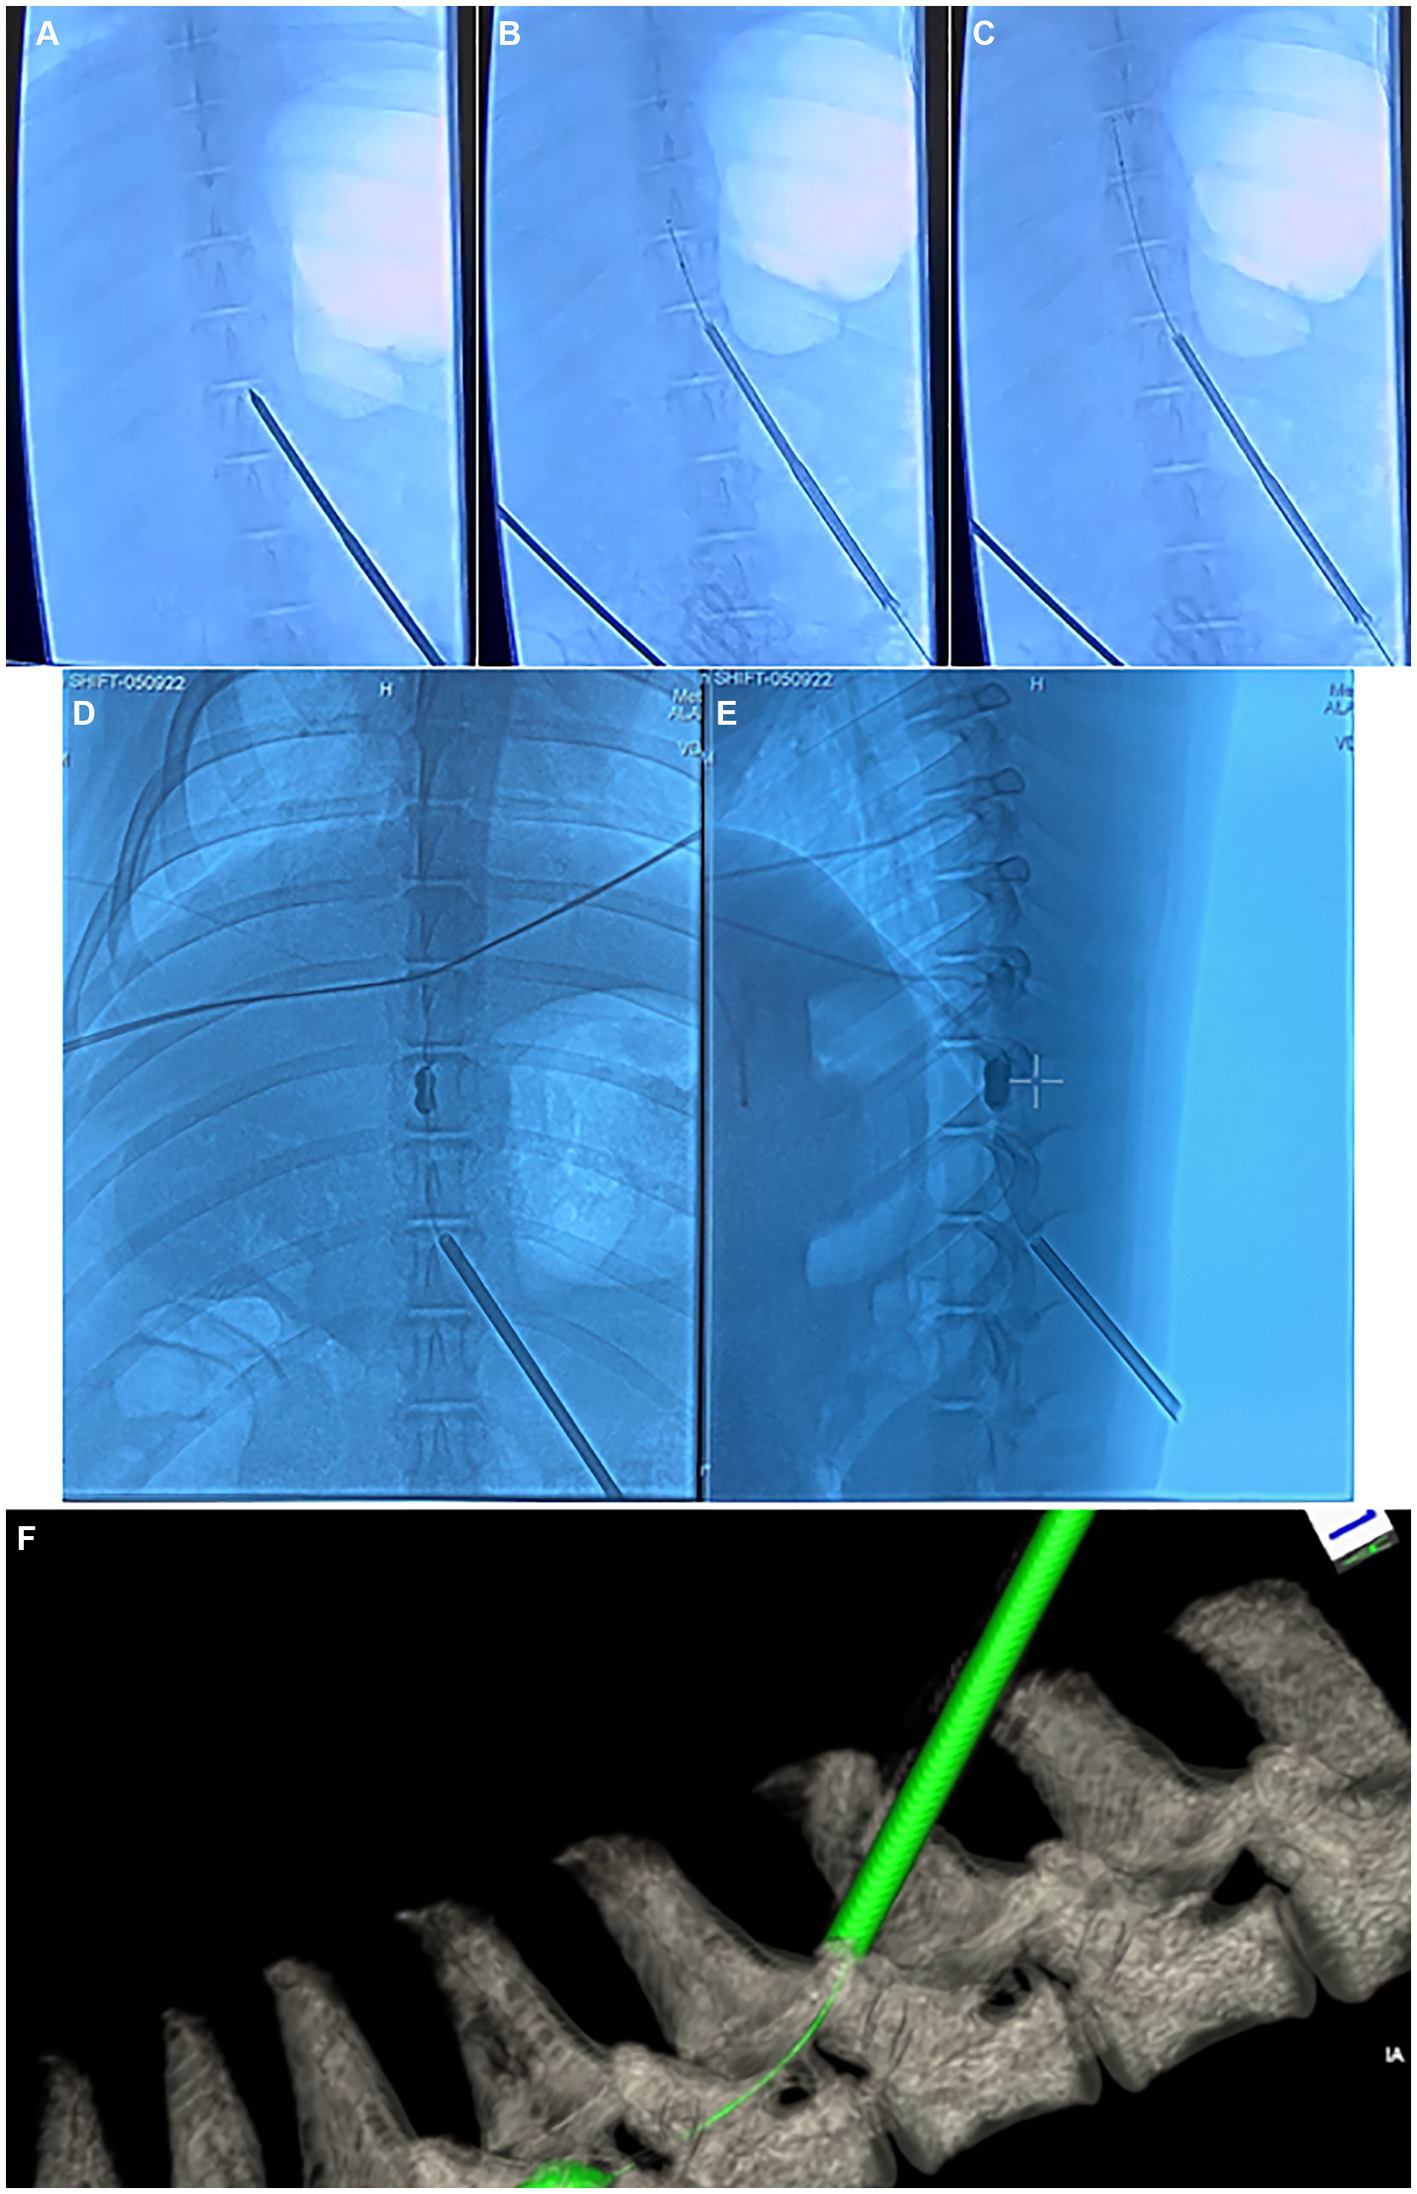

Figure 4

Fluoroscopy and computed tomography (CT) images depicting the injury surgery. (A–C) anterior–posterior (AP) fluoroscopy images depicting the insertion of the Jamshidi needle into the interlaminar epidural space in the thoracic spine, along with deployment of the kyphoplasty cannula into the epidural space. (D) AP and (E) lateral fluoroscopy images depicting inflation of the kyphoplasty balloon within the epidural space. (F) Dyna-CT depicting the kyphoplasty catheter and inflated balloon within the epidural space.

All animals received pre-operative penicillin and underwent general anesthesia via total intravenous technique (TIVA) using propofol in order to allow for testing of evoked potentials. Animals were placed prone on an operating table and were affixed to the table with straps. The T6 level was localized in each animal using fluoroscopy. A small incision was made in the left paramedian T10 area (4–6 cm lateral to the midline) and a Jamshidi needle was introduced into the T8/9 interlaminar space using fluoroscopy. From here, a kyphoplasty balloon (Kyphon, Medtronic, Inc., 8 gauge catheters, 15 mm diameter, 5 cc full inflation volume, 700 psi-rated) was introduced through the Jamshidi needle into the epidural space. The kyphoplasty balloon was advanced until the balloon was seen to be present laterally at the T6 level in order to create a lateralized injury. From here, the balloon was slowly inflated while running continuous motor-evoked potentials (MEPs). Once the MEPs in the lower extremities were seen to be absent, balloon inflation was stopped and the balloon was maintained at its current pressure for 15 min, after which time, the balloon was deflated and the balloon and Jamshidi needle were removed. Balloon inflation pressure amounted to roughly 15 psi in most cases, although inflation volume was not stopped according to balloon pressure, but rather according to the pressure at which MEPs in the lower extremities were abolished. The wound was closed in standard layered fashion. Final skin closure was with a topical skin adhesive. The animal was maintained under anesthesia for a post-injury MRI as well as post-injury neurophysiologic testing, after which time the animal was awoken from anesthesia. Fluoroscopy images depicting the kyphoplasty balloon deployment and inflation within the epidural space are seen in Figure 4.